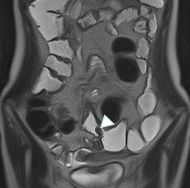

MRエンテログラフィー 2

腸管壁の肥厚と口側拡張を伴った狭窄を認める。

MRエンテログラフィー 3

腸管腸管ろう(小腸造影検査との比較)を認める。